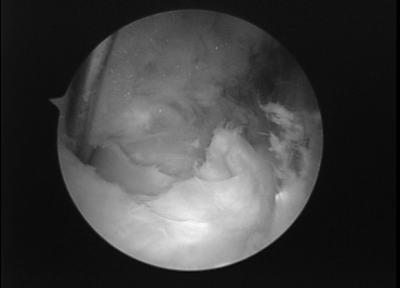

患者,女, 53岁。因“发现左膝肿块2月”入院。体检示左膝腘窝内侧可及4cm*4cm质韧肿块,压痛(-),活动度良好。左膝内侧关节间隙压痛(+),麦氏征(+)。MRI示“左膝腘窝囊肿,左膝内侧半月板损伤”。经完善术前准备后行关节镜治疗术。术中先采用后侧入路,行关节镜下囊肿切除,然后行常规关节镜检查,处理关节腔内半月板损伤,同时经后内侧入路打开腘窝囊肿与关节腔通路。

后路关节镜下切除囊肿,术后次日患者下床活动并出院,术后半年随访显示关节活动良好,未见囊肿复发。